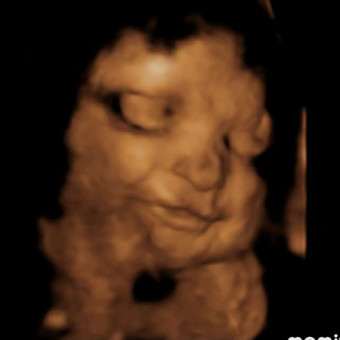

Kanaan Joy’s Baby Registry

Katelyn & Justin Bullock

Thank you so much for celebrating our sweet girl with us! Baby Kanaan Joy is already so loved, and we are incredibly grateful for your prayers, kindness, and support. Feel free to browse to get an idea of the items we like, want, and love as we prepare for her arrival.💗